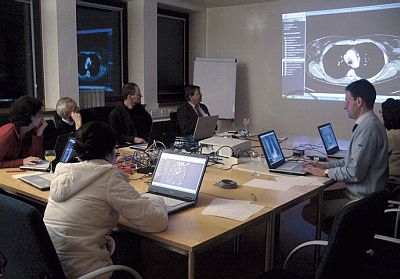

Aktive Fortbildung mit COX beim Frankfurter Intensivkurs 'Lungenkarzinom', 16.11.2007

COX ist die medizinische eLearning-Plattform für die interdisziplinäre Radiologie. Grundlage ist eine umfangreiche radiologische Fallsammlung, die am Institut für Diagnostische und Interventionelle Radiologie (Uni-Klinikum Frankfurt) aufgebaut wird. Mit derzeit ca. 1450 Fällen und 30.000 qualitativ hochwertigen Bildern, viele davon als 3D-Rekonstruktionen, verfügt COX über ein einzigartiges Portfolio.

Durch die Flexibilität, die ein Content-Management-System für die Verwaltung der Inhalte bietet, können einmal produzierte Themen-Module in unterschiedlichen Kurs-Szenarien eingesetzt werden: für CMS, die Studenten-Ausbildung oder die Mitarbeiter-Fortbildung. Durch die Erweiterung der Inhalte mit gruppen- bzw. zeitraum-determinierten Interaktions- Modulen (Chat, Gruppenforen etc.) ist COX mit seiner kurszentrierten Nutzergruppen-Verwaltung die ideale Ergänzung für blended-learning-Kursmodelle. Für Sponsoren und Bildungsanbieter lassen sich Kurse bzw. Kursserien an beliebige Gestaltungsvorgaben anpassen. Neben der kompletten Replikation der Plattform bzw. deren Software-Umgebung lassen sich COX-Kurse durch externe Authentisierungs-Schnittstellen (DocCheck, LDAP etc.) in vorhandene Web-Umgebungen integrieren.